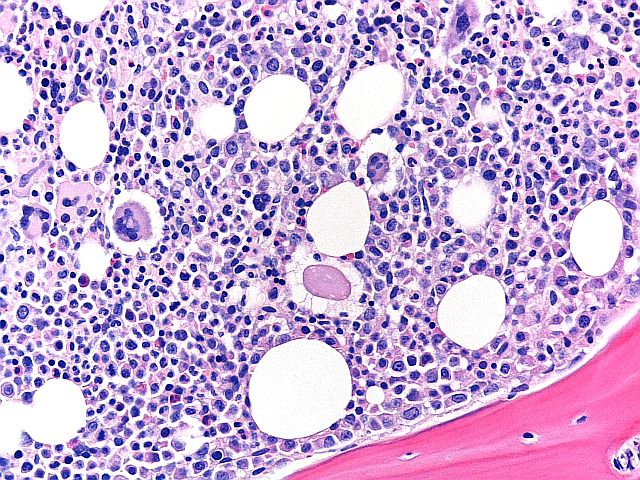

H+E - BMT Scheme

Seen at x20. Overall a very good preperation, but marks were deducted for folds and creases, loss of material, and haematoxylin background staining. This slide scored 8/10.